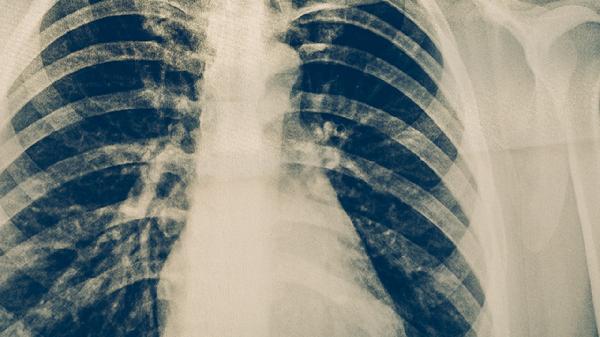

肺结核中途停药可能导致治疗失败、病情复发或产生耐药性。肺结核的治疗需要严格遵循医嘱完成全程用药,突然停药会破坏药物对结核分枝杆菌的持续抑制作用。

肺结核治疗通常需要6-9个月的联合用药,中途停药会使体内残留的结核菌重新活跃繁殖。这些细菌可能对之前使用的药物产生耐药性,导致后续治疗难度增加。部分患者可能出现咳嗽加重、低热、盗汗等症状复发,严重时可能引发肺组织广泛破坏或播散至其他器官。

极少数情况下,中断用药可能导致结核菌产生广泛耐药性,此时可选择的治疗药物非常有限。这类患者可能需要接受更长时间的二线药物治疗,甚至面临治疗无效的风险。耐药结核病的传播还会对公共卫生安全造成威胁。

肺结核患者应每日定时定量服药,即使症状消失也不可自行停药。治疗期间出现药物不良反应时,应及时与医生沟通调整方案而非擅自中断。完成全程规范治疗是治愈肺结核的关键,同时需定期复查痰菌和影像学评估疗效。保持均衡饮食、充足休息和良好通风环境,有助于增强治疗效果。